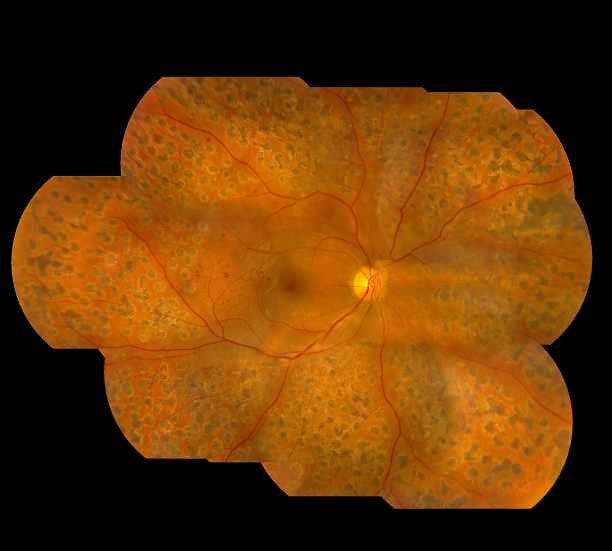

而我們的視網膜布滿了大量的微絲血管,如果血糖長期不穩定,有可能導致視網膜血管內皮細胞遭到破壞,進而引發一系列的眼底病變,如微血管瘤、糖尿黃斑水腫、視網膜新生血管,甚至視網膜脫落或青光眼,這些眼疾若未及時治療,嚴重情況下有失明的危險。

上海眼科醫院排名醫生提醒:糖網病早期癥狀不明顯,建議糖尿病患者定期檢查眼底,如果能及早發現并進行針對性治療,可較大程度地保護我們的視力。